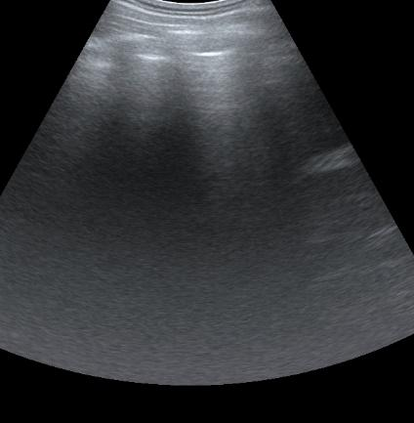

Most deep neural networks (DNNs) based ultrasound (US) medical image analysis models use pretrained backbones (e.g., ImageNet) for better model generalization. However, the domain gap between natural and medical images causes an inevitable performance bottleneck. To alleviate this problem, an US dataset named US-4 is constructed for direct pretraining on the same domain. It contains over 23,000 images from four US video sub-datasets. To learn robust features from US-4, we propose an US semi-supervised contrastive learning method, named USCL, for pretraining. In order to avoid high similarities between negative pairs as well as mine abundant visual features from limited US videos, USCL adopts a sample pair generation method to enrich the feature involved in a single step of contrastive optimization. Extensive experiments on several downstream tasks show the superiority of USCL pretraining against ImageNet pretraining and other state-of-the-art (SOTA) pretraining approaches. In particular, USCL pretrained backbone achieves fine-tuning accuracy of over 94% on POCUS dataset, which is 10% higher than 84% of the ImageNet pretrained model. The source codes of this work are available at https://github.com/983632847/USCL.